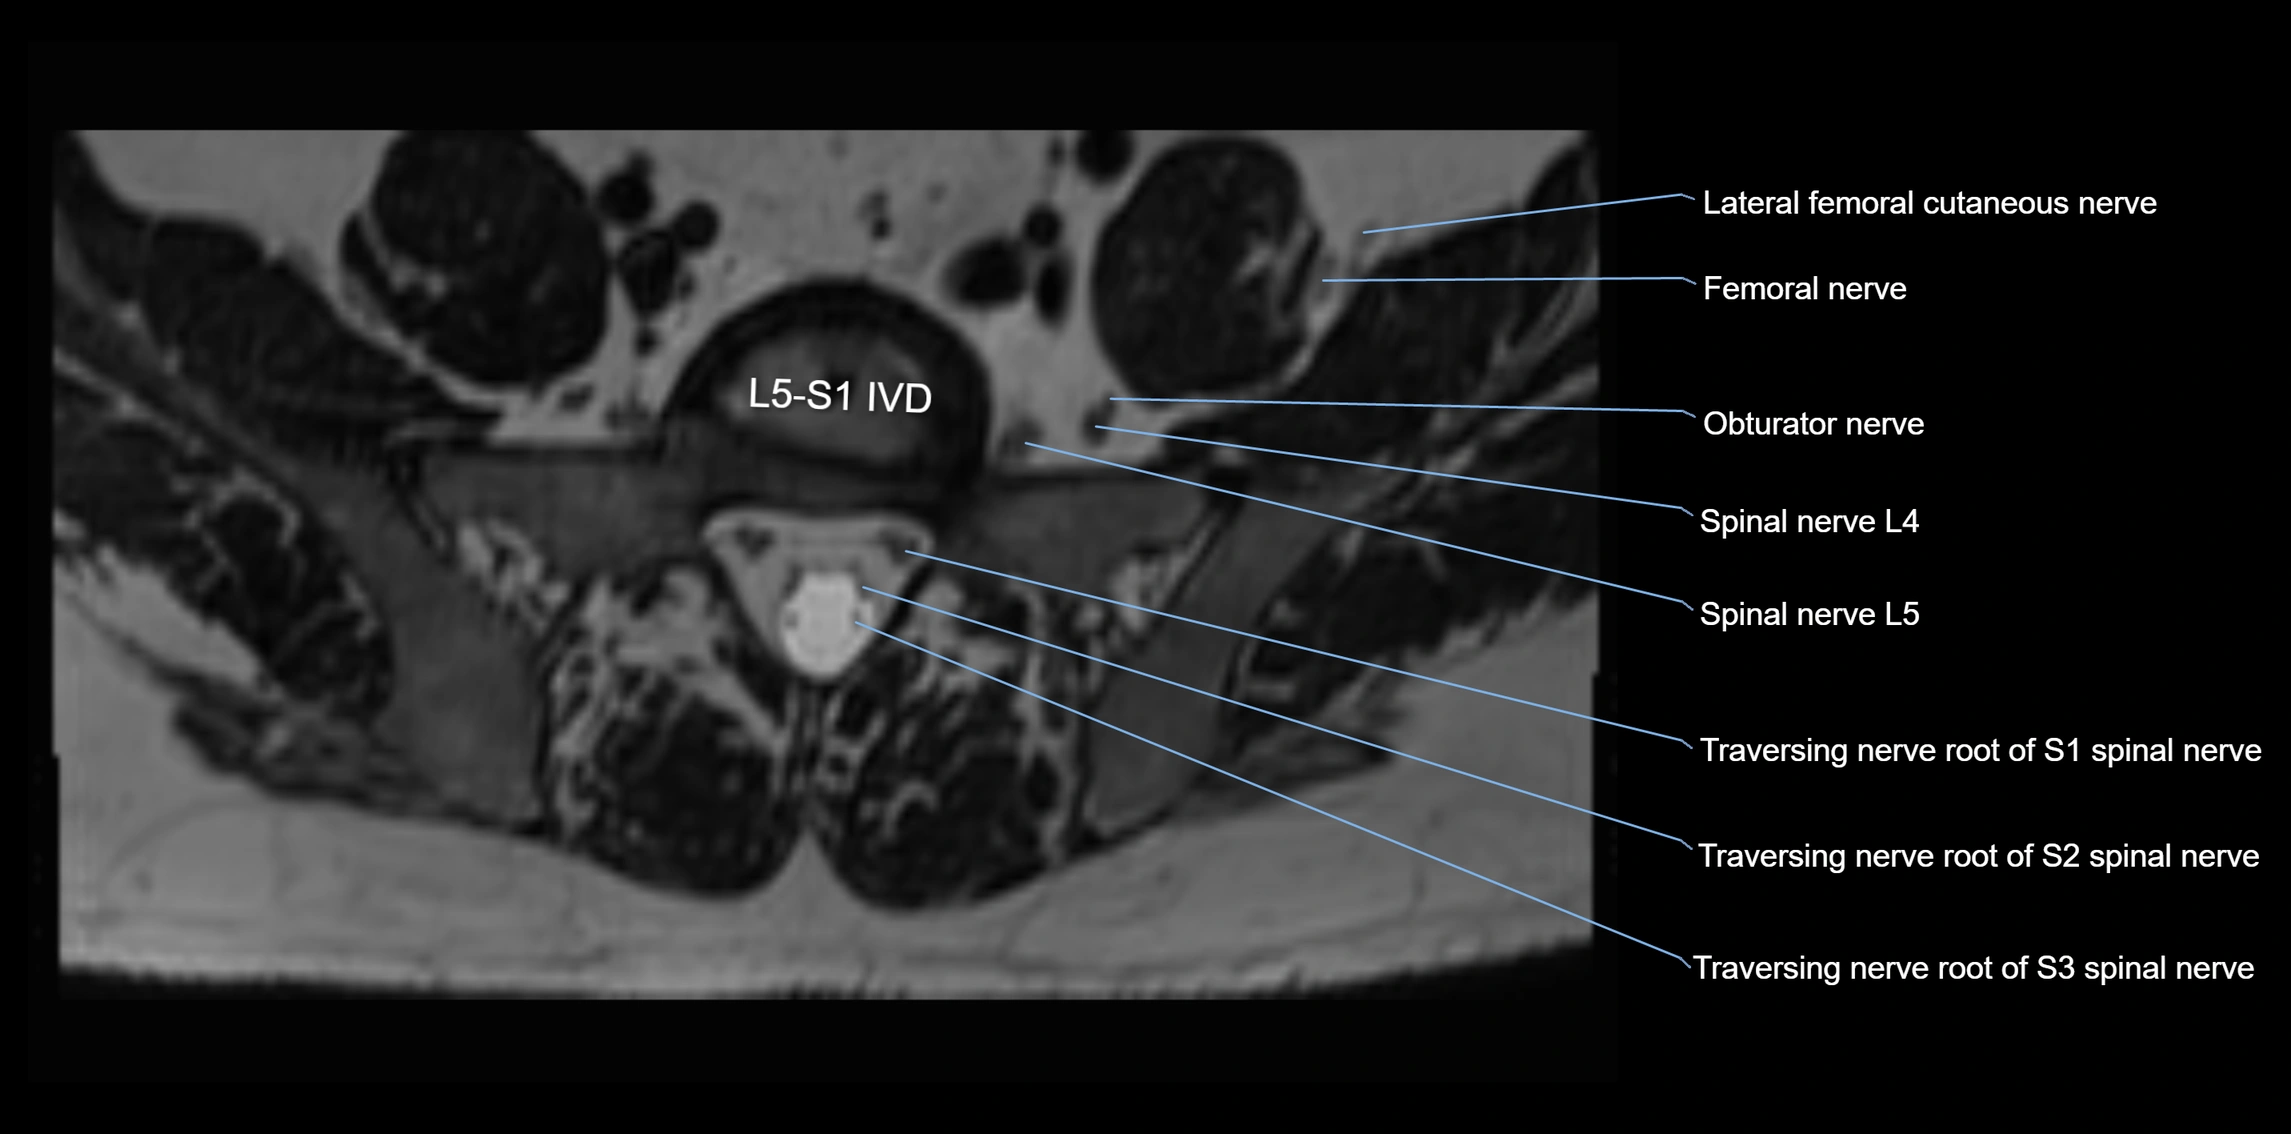

MRI Appearance

T1-weighted images:

• Nerve appears as a very thin low-to-intermediate signal intensity structure

• Surrounded by bright fat, aiding visualization

T2-weighted images:

• Nerve shows intermediate to mildly hyperintense signal compared to muscle

• Pathological involvement appears brighter

STIR (Short Tau Inversion Recovery):

• Normal nerve appears dark

• Inflamed or entrapped nerve appears bright hyperintense

T1 Fat-Sat Post-Contrast:

• Normal nerve enhances minimally

• Pathologic nerve (neuritis, entrapment, tumor infiltration) shows focal or diffuse enhancement

3D T2 SPACE / CISS:

• Nerve appears intermediate to mildly hyperintense compared to muscle

• Surrounded by bright fat or CSF, improving visualization

• Best sequence for mapping small pelvic nerves such as the anococcygeal